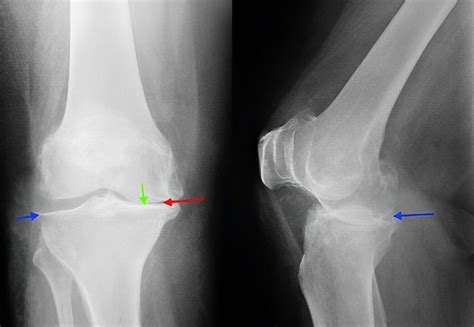

Ankstesni diagnostikos metodai, tokie kaip rentgenografija, dažnai būdavo nepakankamai informatyvūs diagnozuojant sinovines hemangiomas. Rentgenogramos paprastai parodo tik kaulų struktūras ir gali atskleisti tik minkštųjų audinių patinimą, bet nepaaiškina jo priežasties. Tomografinė kompiuterinė tomografija (KT) gali suteikti daugiau informacijos apie minkštuosius audinius, tačiau jos gebėjimas vizualizuoti smulkias kraujagyslių anomalijas ir jų santykį su aplinkiniais audiniais yra ribotas, be to, ji susijusi su jonizuojančiosios spinduliuotės poveikiu.

Rezultatai parodė, kad radiografijos neatskleidė jokių anomalijų, išskyrus minkštųjų audinių patinimą 8 atvejais. KT tyrimas taip pat nebuvo pakankamai informatyvus. Tačiau visais 7 MRI tyrimo atvejais buvo tiksliai nustatyta hemangiomos vieta, jos santykiai su intraartikulinėmis struktūromis, o 3 atvejais buvo pastebėta ir ekstraartikulinė naviko dalis.